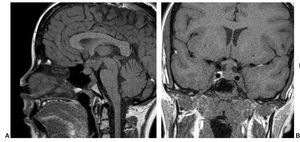

Paciente varón de 14 años de edad, con talla baja y panhipopituitarismo.

Fig. 1.